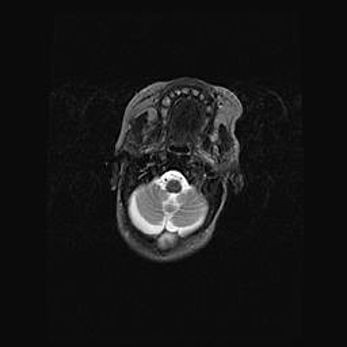

Аномалия Денди-Уокера. Признаки гипоплазии мозолистого тела.

Возраст: 5 месяцев 3 дня

Вес: 5550 г

Пол: мужской

Окружность головы: 39 см

Срок гестации: 40 недель

Аномалия Денди-Уокера – это порок развития головного мозга, для которого характерна триада симптомов: гипотрофия или аплазия червя мозжечка и/или полушарий мозжечка, расширение четвёртого желудочка с формированием ликворной кисты задней черепной ямки, гипертензионная гидроцефалия различной степени.

Гипоплазия мозолистого тела относится к дефектам внутриутробного этапа развития мозговой ткани, возникающим в процессе закладки структур головного мозга, что происходит на начальных этапах развития эмбриона.